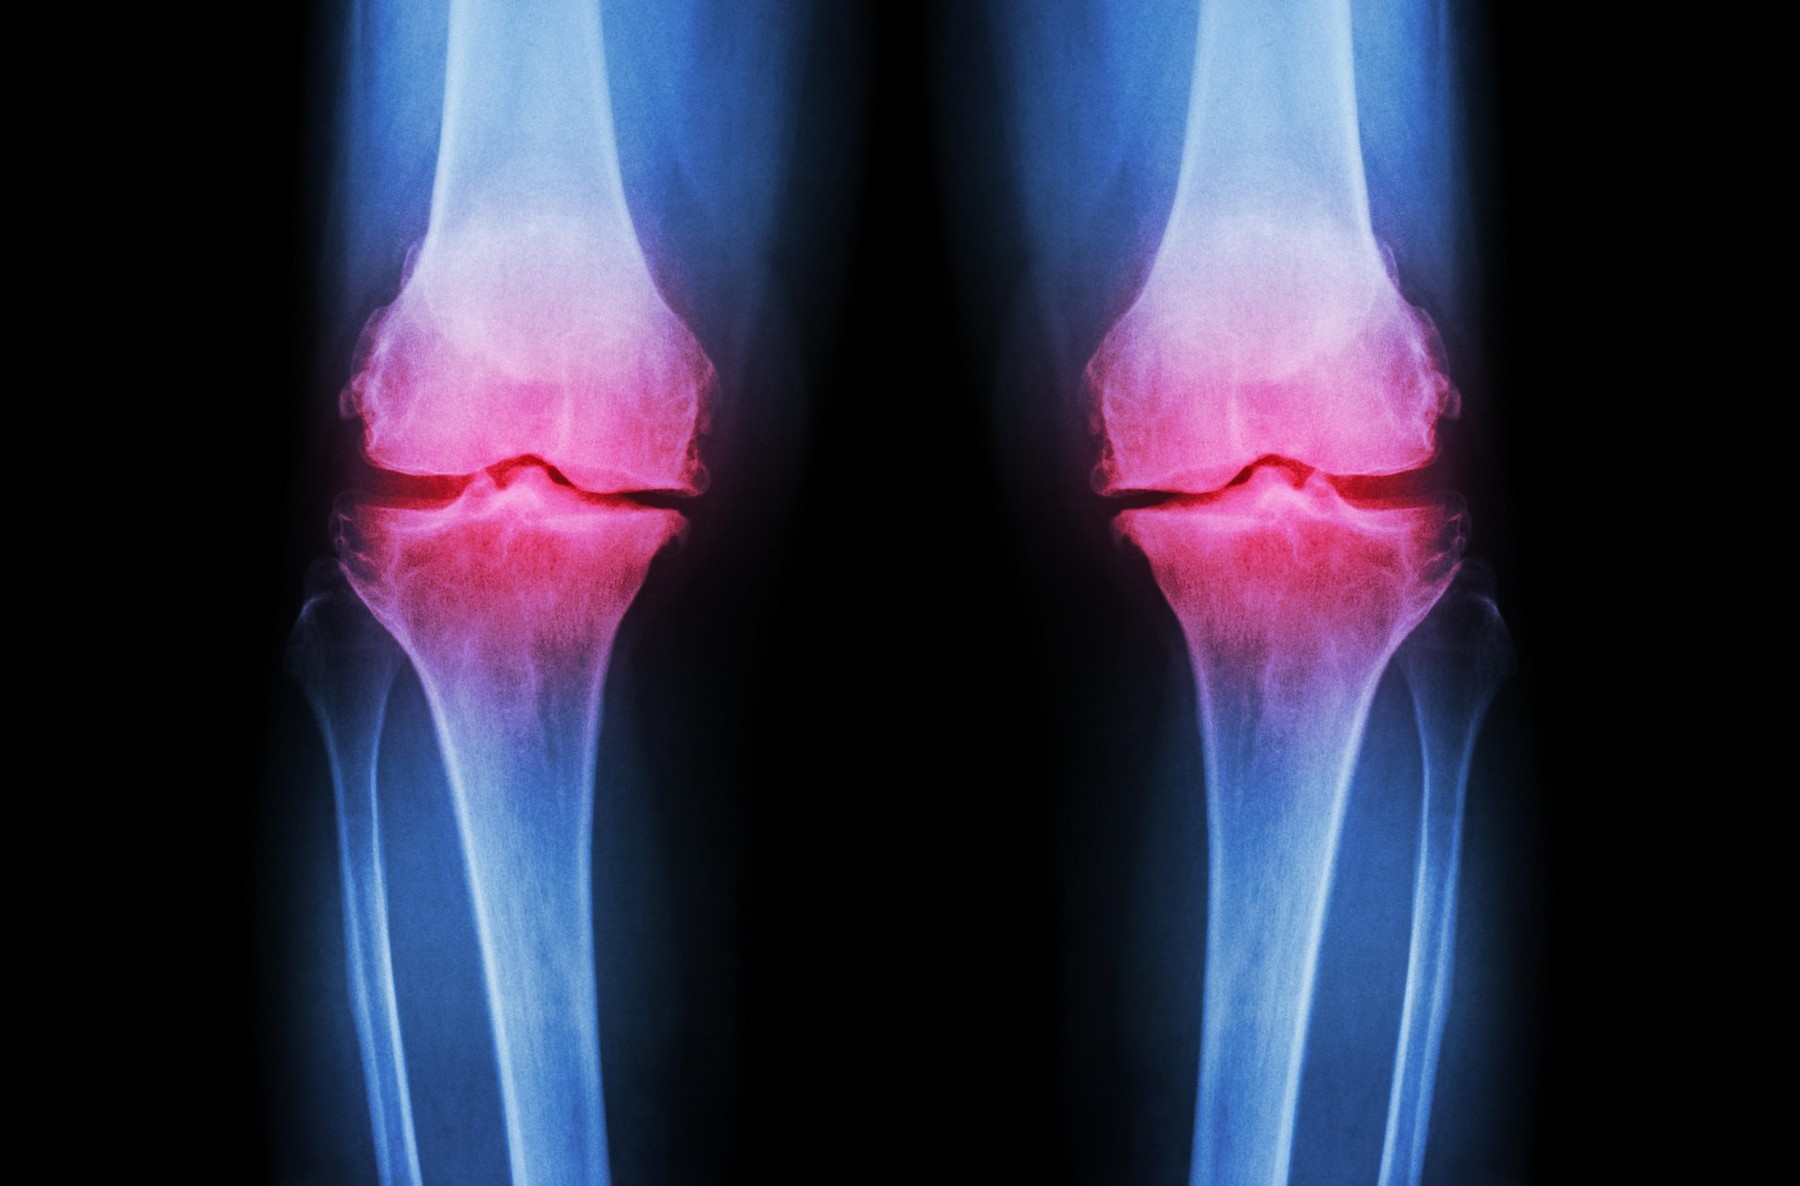

Osteoartroza in ostaeoartritis sta degenerativni bolezni sklepov, ki ju zaznamuje obraba ter propadanje hrustanca in okoliških struktur. O osteoartritisu govorimo takrat, ko je poleg obrabe hrustanca prisotno še vnetje.

Pogostost obeh težav s staranjem prebivalstva vse bolj narašča. Po 70. letu starosti naj bi omejena gibljivost in bolečine v sklepih mučile že približno 40 odstotkov ljudi. Število ljudi, ki iščejo rešitev za svoje težave s sklepi, je čedalje večje.

Obstoječi nabor zdravil in zdravljenj ni sposoben dolgoročneje zavreti ali celo odpraviti težav. Zadnje zatočišče je zamenjava prizadetega sklepa z umetnim. Zato je navdušenje nad novo, potencialno prebojno terapijo z matičnimi celicami, do neke mere razumljivo.